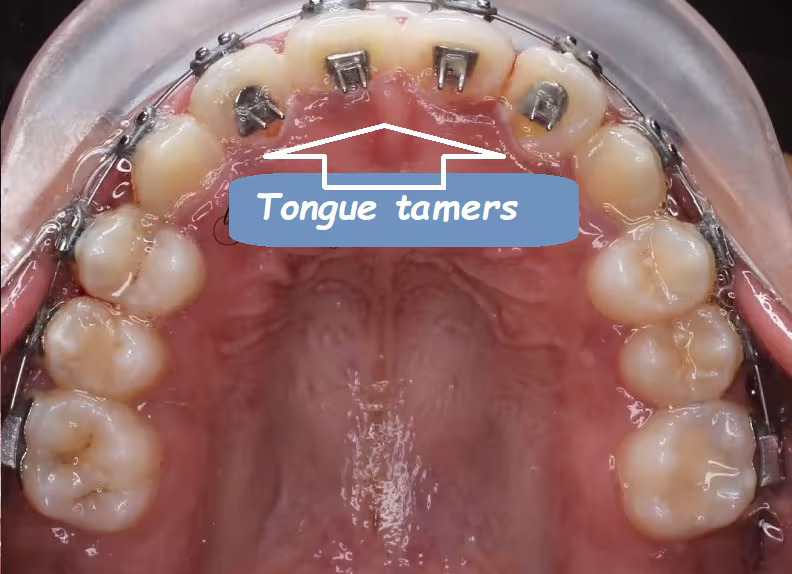

۳. ابزارهای عادتشکن (Habit Breakers)

این وسایل یا بهصورت ثابت (Fixed) توسط ارتودنتیست نصب میشوند یا به شکل متحرک برای استفاده در طول روز تجویز میگردند. ابزارهای عادتشکن معمولاً در موارد مکیدن انگشت یا فشار زبان به کار میروند و مانع تماس مستقیم با دندانها میشوند.

مدت استفاده معمولاً چند ماه است تا رفتار ناهنجار بهطور کامل ترک شود.